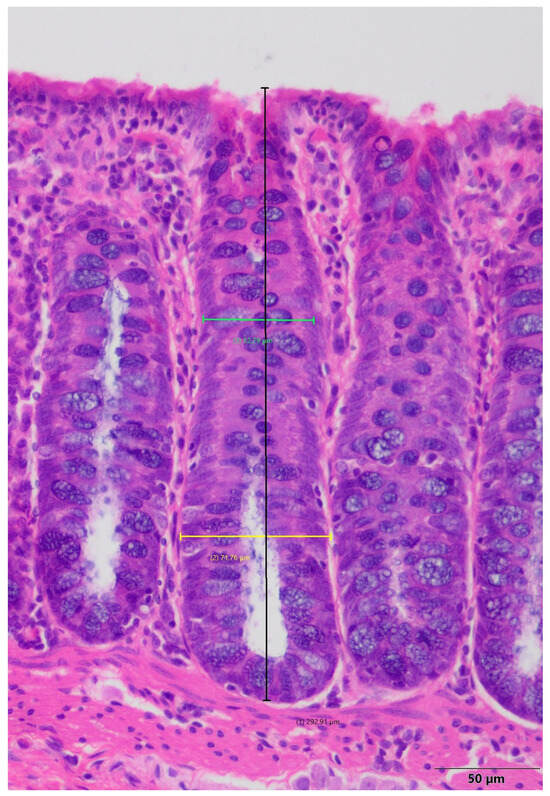

Inflammatory bowel diseases (IBD), such as Crohn’s disease (CD) and ulcerative colitis (UC), are chronic, progressive conditions with increasing prevalence worldwide. The aim of this study was to evaluate the usefulness of a porcine model of colitis induced by 2,4-dinitrobenzenesulfonic acid (DNBS) as [...] Read more.

Inflammatory bowel diseases (IBD), such as Crohn’s disease (CD) and ulcerative colitis (UC), are chronic, progressive conditions with increasing prevalence worldwide. The aim of this study was to evaluate the usefulness of a porcine model of colitis induced by 2,4-dinitrobenzenesulfonic acid (DNBS) as a translational model of IBD. Sixteen Polish White pigs were divided into a control group and colitis group. Colitis was induced by rectal administration of DNBS (80 mg/kg in 50% ethanol). Clinical status, hematological and biochemical parameters, fecal calprotectin levels, cytokine plasma concentrations, and histopathological changes in the gastrointestinal tract were evaluated. DNBS administration resulted in persistent diarrhea and mild abdominal pain without general deterioration of health. Significant increases in fecal calprotectin levels and aspartate aminotransferase (AST) activity were observed. Histopathological changes in the colon were limited to the mucosa, which is similar to human UC, while the mild changes observed in the ileum indicate similarity to CD. This model is characterized by moderate inflammation, high reproducibility, and low mortality, making it valuable model in translational research on IBD. Full article